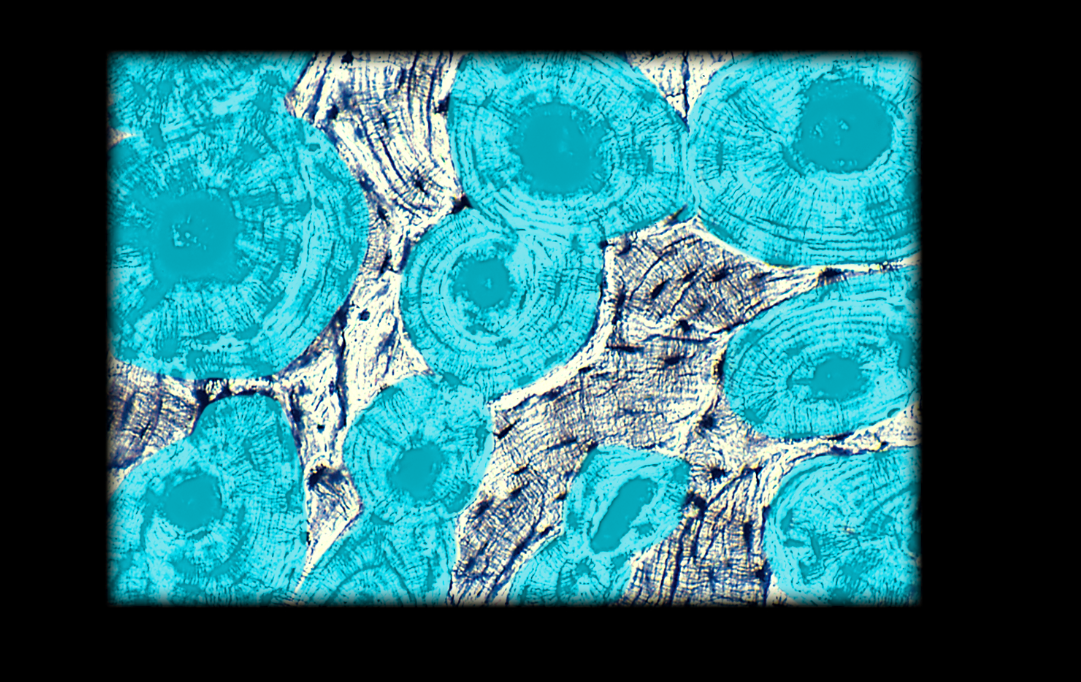

Osteocyte

Lacuna (with chondrocyte) in hyaline cartilage

Osteon

Chondrocyte (in lacuna) in hyaline cartilage